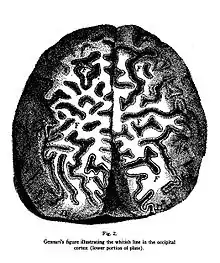

Francesco Gennari (born 4 October 1750 Mattaleto di Langhirano; died 4 December 1797) was an Italian anatomist. He is known for line of Gennari, a macroscopically white band seen in the cerebral cortex of the occipital lobe, which he observed on 2 February 1776 in the course of examining ice-frozen sections of unstained human brain during his study in medical school. He mentioned it in his book De peculiari structura cerebri, nonnulisque ejus morbis (1782), and referred to it as lineola albidior.

None of the anatomists I happened to read have taught that in addition to the cortical and medullary substance there is in the brain another substance which I am accustomed to call the third substance of this organ. ... it can be found with difficulty or it is somewhat obscure in the anterior part of the brain, but it can be detected more and more clearly in the posterior part of the brain.[1]

The discovery of this part of the brain is considered the first evidence that the cerebral cortex was not uniform in structure.[2]